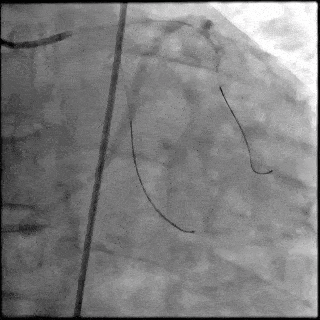

【DSA图 回旋支导丝顺利通过病变】

5月28日8:00,葛均波院士团队在中山医院16号楼16楼中伟厅成功连线喀什二院导管室,沪喀远程手术正式开始。8:35,新疆喀什二院导管室内股动脉入路通路建立后,行左右冠脉造影示左前降支中段存在85%的严重狭窄,狭窄位于血管分叉路口且紧邻心肌桥;且左回旋支中段近乎闭塞,血管细窄且迂曲,病变弥漫。8:59,葛院士于上海操控血管介入机器人主端PANVIS COF,将指引导管送至左冠脉开口,并操控主支导丝和分支血管保护导丝通过狭窄病变,后送至前降支和对角支血管远端以建立轨道,同时利用介入机器人的微速调整功能避开心肌桥,以亚毫米级精准定位释放1枚支架。在成功处理患者左前降支病变后,葛院士通过搓捻机械操纵杆,远程精细调整导丝“进攻”方向,顺利通过左回旋支次全闭塞病变。因血管相对细小且病变弥漫,葛院士决定采用单纯球囊扩张术处理,即刻造影提示几乎无残余狭窄,避免了额外的支架植入。10:10,撤出所有导丝及导管,手术顺利结束。